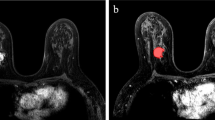

Among all the available imaging techniques, MRI is non-invasive, generally well-accepted and routinely used in clinical practice for BC staging. For axillary staging, MRI is unaffected by patient habitus and less operator-dependent than US, demonstrating the best visualization of the entire axilla (Baltzer et al. 2011).

Typical MRI suspicious features include: lymph node size, morphologic features (cortical thickening, loss of fat hilum, irregular margins, and round shape), presence of peripheral edema and asymmetry with the contralateral axilla (Baltzer et al. 2011). Through the combination of MRI pure information routinely used in breast cancer staging and radiomic features, unnecessary ALND and SLNB could be avoided, with a reduction of surgical complication rate and improvement of patient's quality of life. In addition, radiomic signatures applied to MRI could be a step toward more personalized and precision medicine in treatment strategies for breast cancer patients. Some studies have also developed nomograms, that are graphical representations of the mathematical relationship between prognostic factors, both clinical and diagnostic, including radiomic features, to visually aid the clinical decision process (Balachandran et al. 2015).

Among breast MRI sequences, DCE is considered the best for primary tumor identification and characterization, although the diagnosis of metastatic lymph nodes by MRI is still not ideal. However, the current literature indicates promising results in terms of predicting metastatic axillary lymph nodes using MRI radiomic signatures in breast cancer patients, particularly using DCE sequences. Currently, DWI sequences are rarely used alone in radiomics studies because of relatively low image quality and spatial resolution, leading to less quantitative data availability. Among all the studies analyzed by this review, one includes DWI sequences with T2-FS as pre-contrast sequences (Dong et al. 2018), one is based only on T2-FS images (Tan et al. 2020) and two studies combined DWI and T2-FS images with DCE sequences (Chai et al. 2019; Yu et al. 2020).

Feature extraction of radiomics usually requires prior segmentation. Although studies in which ROIs are manually drawn by radiologists may be more prone to error and user variability, prediction is still good, despite being a time-consuming method. It would be ideal to develop a reliable and validated automatic segmentation method, but it is not yet available.